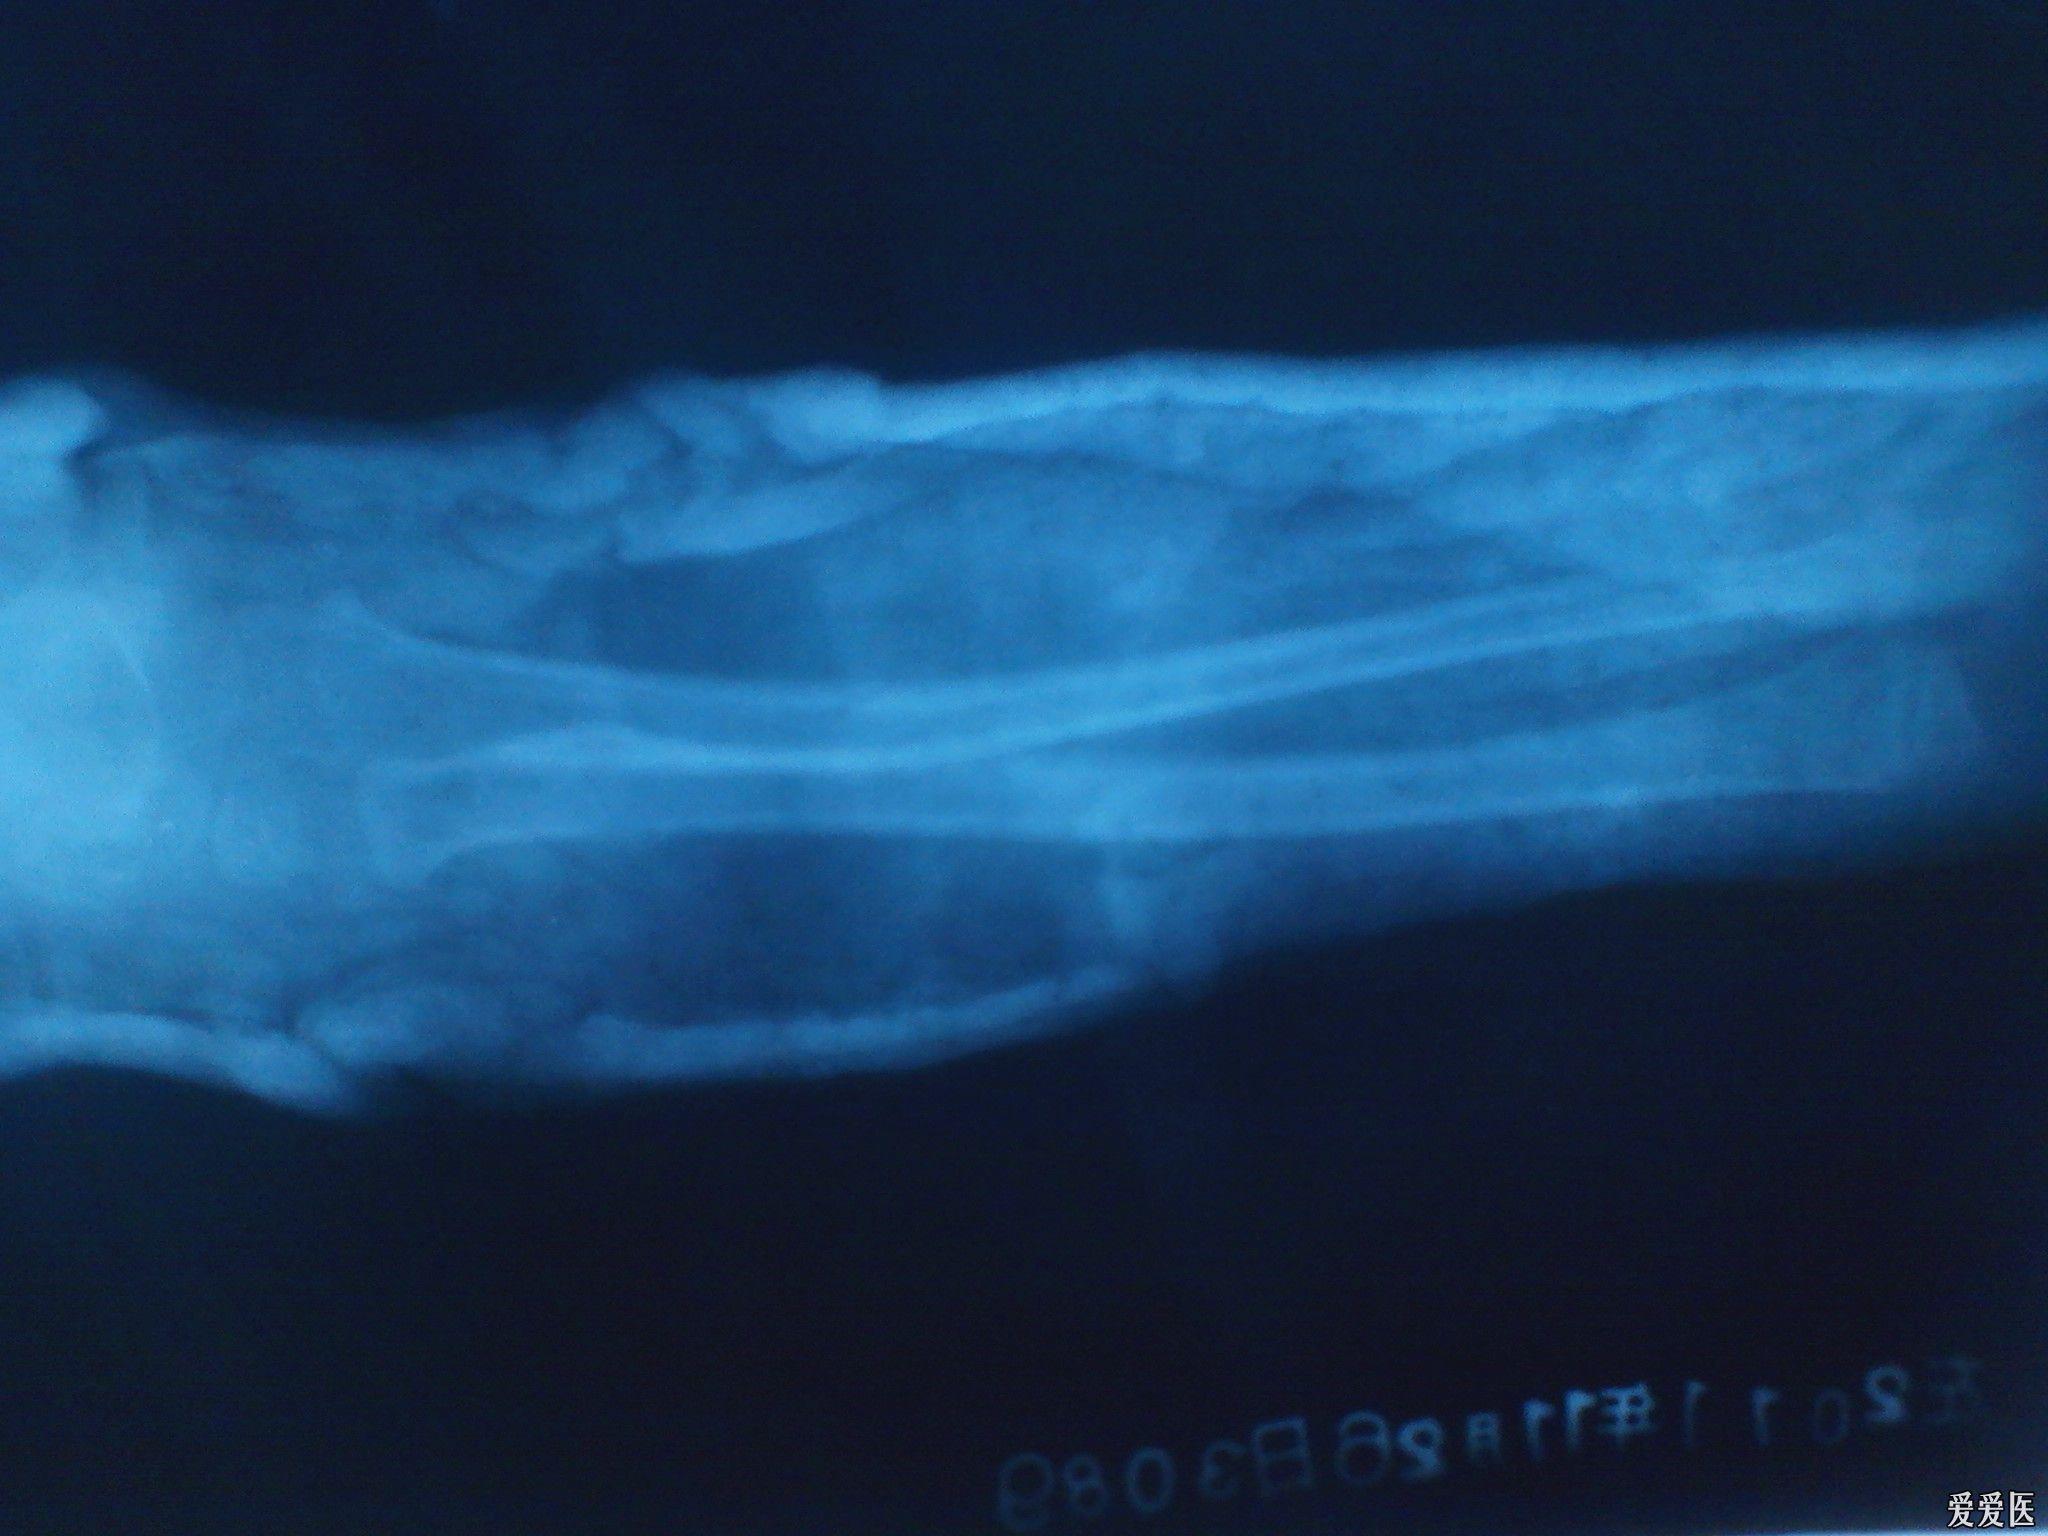

桡骨近端骨折的手术治疗

图片尺寸3456x4608